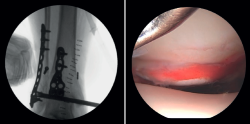

- Valoración de la reducción del maléolo posterior: con la artroscopia podemos verificar la reducción del maléolo posterior(5) (Figura 2).

Lee describe una técnica novedosa que utiliza una guía de broca con la artroscopia de tobillo para la reducción de fragmentos articulares en fracturas del maléolo posterior. En particular, esta técnica es beneficiosa para pacientes con fracturas trimaleolares que presentan un fragmento articular deprimido, ya que permite una reducción anatómica y minimiza la necesidad de incisiones extensas(11). - Extracción de cuerpos libres. La presencia de cuerpos libres dentro de la articulación es un hallazgo común en las fracturas de tobillo. El 33% de los pacientes con artroscopia presentaron cuerpos sueltos intraarticulares retirados durante la intervención (24 de 71 casos)(12). La artroscopia permite la eliminación precisa de los cuerpos libres intraarticulares, los cuales pueden producir dolor, bloqueo o limitación de la movilidad y daño del cartílago articular(13).

Figura 3. A: cuerpos libres; B: lesión osteocondral; C: reducción de la lesión osteocondral; D: estimulación medular.